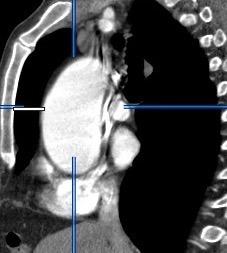

Aneurisma aórtico de localización poco habitual

Edad: 40-50 años

3% segregan catecolaminas.

(En el área Paravertebral +/-50%.)

Intenso realce con el contraste.

32 años .Preeclampsia a los 19. Hipertensión no controlada. Masa paravertebral sólida que se realza intensamente con afectación ósea.

Yue Y t al. Asymptomatic left posterior mediastinal functional Paraganglioma. A case report. Medicine . 2019